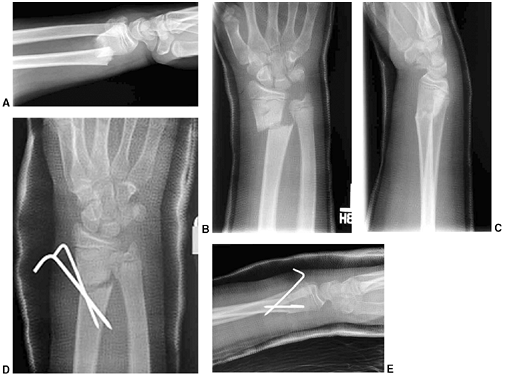

Before surgical excision, it is necessary to clearly delineate the

extent and location of the bar. Plain radiography should be performed

with the beam centered on the growth plate and tilted in the same plane

as the growth plate. Helical computed tomographic scanning and MRI have

largely replaced traditional tomography (49). Three-dimensional reconstruction using these techniques allows accurate identification of the size and location of the bar (50).

![]() |

Figure 33.5 Physeal bar resection. A: A distal physeal bar is depicted in this anteroposterior hypocycloidal tomogram. B:

This condition was treated with bar excision and insertion of Cranioplast. Five months later, the physis remains open, and the two metal markers inserted at the time of surgery are 28 mm apart. There is residual femoral tibial valgus deformity. C: Four years later, there has been some improvement in the femoral tibial alignment, and growth of the distal femur has resumed. The markers are 83 mm apart. |